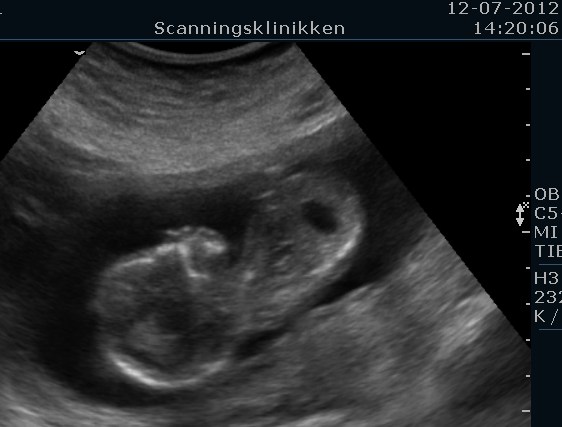

Her er et par billeder. Det første billede viser at man slet ikke er i tvivl om at det er en dreng og det andet billede viser at han har det sødeste lille fine hoved med runde kinder og kyssemund